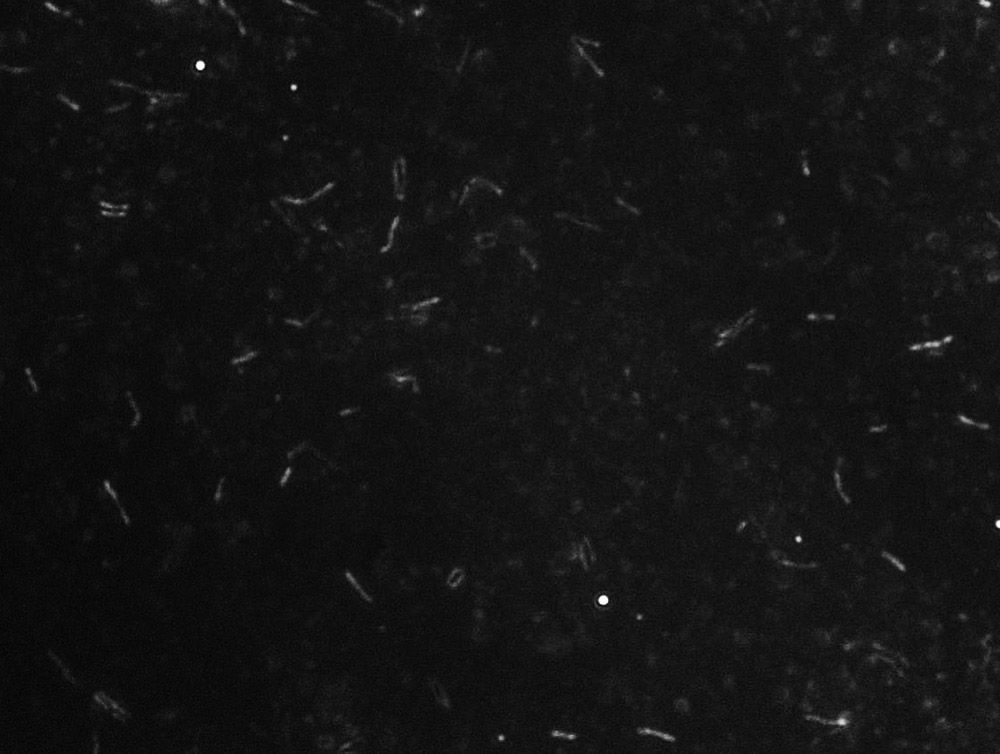

Figure 2.

Photomicrograph of Mycobacterium tuberculosis bacteria in the sputum sample from Elisha Howland, collected May 20, 1892, and mounted by Frank A. Rogers (see Figure 1). Courtesy of Nerina Jusufovic, imaged with a darkfield illumination, a 40x objective lens, and a C-mounted digital camera on an Olympus BX51 microscope.